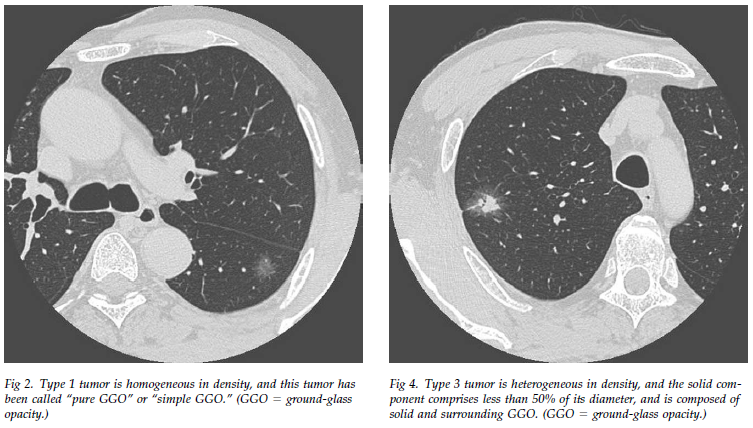

The solid (or consolidation) component was defined as an area of increased oPACIFICation more than 5 mm in diameter, which completely obscured underlying vascular markings.

Ground-glass opacity was defined as an area of a slight, homogeneous increase in density, which did not obscure underlying vascular markings.

Semiconsolidation was defined as an area of an intermediate homogeneous increase in density, which did not obscure underlying vascular markings.

截图202305041407176329.png

截图202305041407403945.png